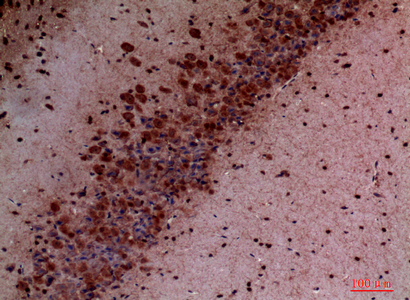

Immunohistochemistry analysis of paraffin-embedded mouse brain using PI3 Kinase p110 delta antibody.High-pressure and temperature Sodium Citrate pH 6.0 was used for antigen retrieval.